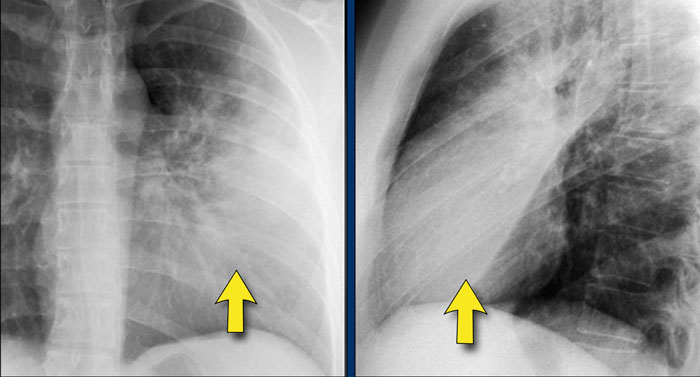

Hidden Areas (3): Pneumonia Below the Diaphragm

In this case, a pneumonia was primarily located below the right diaphragmatic dome (yellow arrow), within the posterior basal segment of the right lower lobe.

• On the lateral view, there is an increase in opacity over the lower thoracic vertebrae, indicating lower lobe consolidation (arrow).

• Again, image magnification may be necessary for adequate assessment.